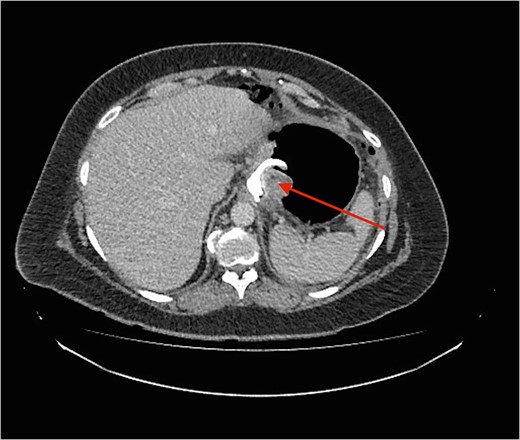

Cross section CT image demonstration the site of the band with no collection (red arrow).